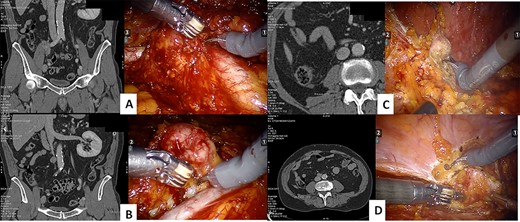

The procedure started with the excision of the right common iliac lymph nodes and then moving to the iliac bifurcation lymph nodes. The surgery continued with the access to the interaortocaval space, with the excision of a 4 cm mass where the IVC was carefully defined with meticulous dissection to prevent inadvertent violation (Fig. 1). At last, the procedure continued with the excision of retroperitoneal fat of the right renal fossa and of a 2 cm peritoneal nodal recurrence.

CT scan and intraoperative image of the: iliac bifurcation lymph node recurrence (A), the interaortocaval space lymph node recurrence (B), the renal fossa recurrence (C) and the peritoneal recurrence (D)

The operative time was 114 min, and estimated blood loss was 200 ml. The abdominal drainage was removed at first postoperative day. The length of hospital stay was 3 days. No complications occurred.